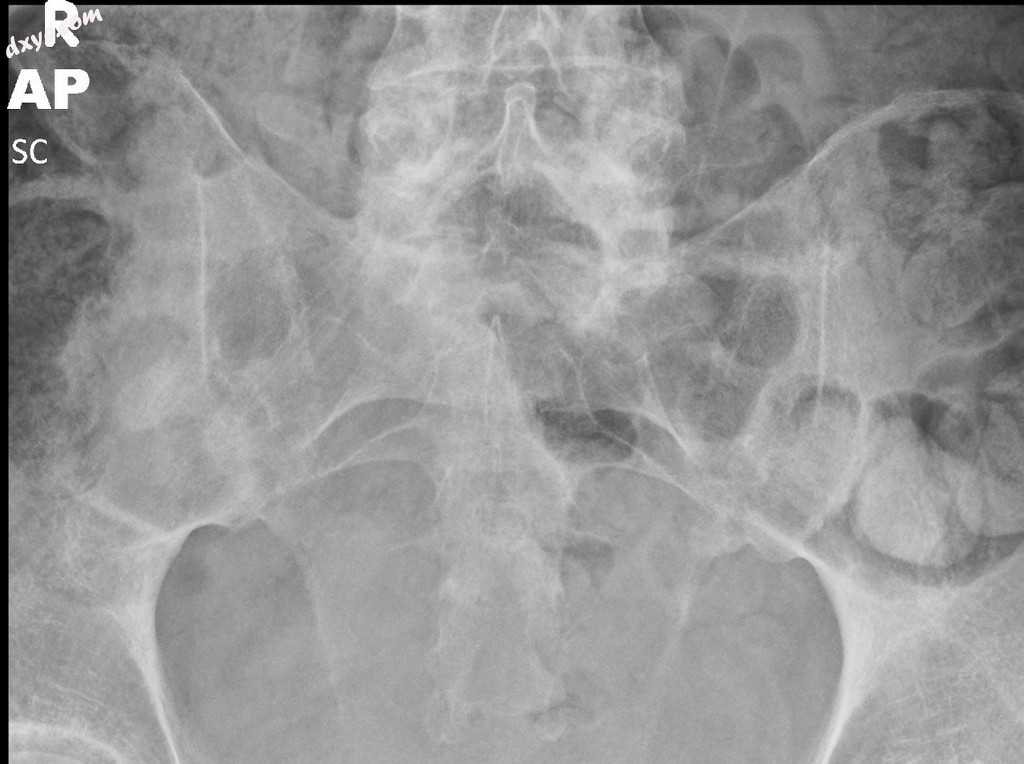

2.jpeg

正位

骶髂关节完全强直。

在已知的强直性脊柱炎患者中,骶髂关节完全强直是先前骶髂关节炎过程的末端。

射线照相特征

平片

传统的放射成像仍然是第一线的成像,尽管其敏感性和特异性较差的早期疾病。具体的骶髂关节视图有助于评估和比较两侧骶髂关节。

射线照片结果包括:

终板硬化,尤其是髂骨侧终板硬化

不规则接头端板

关节间隙加宽